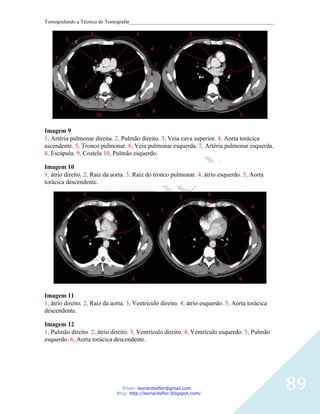

É um tubo fibroso muscular com cerca de 20 anéis cartilaginosos em forma de C, que

mantém a via aérea aberta evitando que a traquéia colabe durante a inspiração.

Localizada anteriormente ao esôfago, da junção com a laringe ao nível de C6 até o nível de

T4 ou T5 onde se divide nos brônquios fonte direito e esquerdo.

Glândulas localizadas próximo ao sistema respiratório: tireóide, paratireóides e o timo.

Tireóide: localizadas anteriormente na região do pescoço logo abaixo da laringe. Bastante